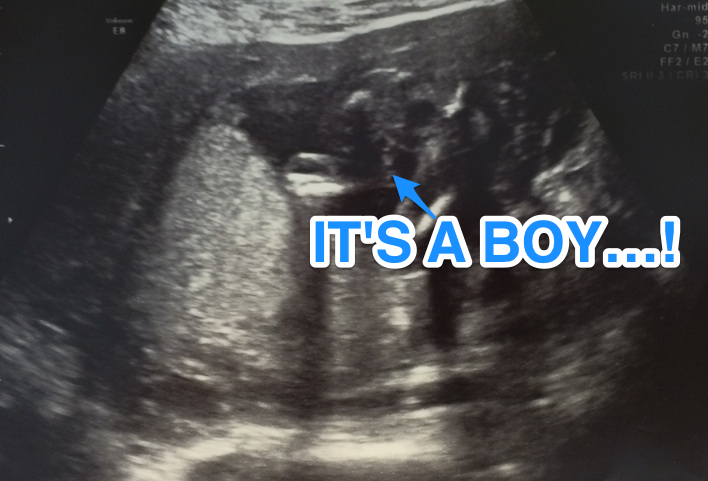

The answer to that question is yes. Can you tell if baby has down syndrome ultrasound? An ultrasound test measures nuchal translucency.

An Ultrasound Can Detect Fluid At The Back Of A Fetus's Neck, Which Sometimes Indicates Down Syndrome.

How soon can you tell if your baby has down syndrome? The ultrasound test is called measurement of nuchal translucency. Yes, extended cisterna magnas in an infants brain can be detected with ultrasound scans around the 20 week mark.

The ultrasound test is called measurement of nuchal translucency. The ultrasound test is called measurement of nuchal translucency. As well as other conditions, one condition of this marker is downs syndrome david portnoy

The ultrasound test is called measurement of nuchal translucency. Can you tell if a baby has down syndrome in an ultrasound? It's usually done between the 10th and 13th week of pregnancy.

Ultrasound can detect fluid at the back of a fetus’ neck, which can be an indicator of down syndrome. During the first trimester, this combined method results in more effective or comparable detection rates than methods used during the second trimester. An ultrasound test measures nuchal translucency.